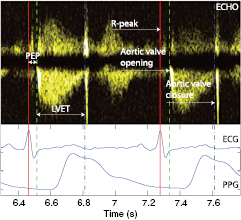

The ECG and PPG signals were recorded with an HP-CMS monitor and stored on a laptop at a sampling frequency of 500 Hz and 125 Hz, respectively. ECHO (in Doppler mode, with ECG) was conducted using a Vivid 7 system from General Electric, which produces images with a temporal resolution of 500 Hz (figure 9). The ECG signals acquired simultaneously by the two systems described above were used to synchronize the signals streams.

Figure 9. Annotation of aortic valve timings using Doppler mode ECHO.

A clinical expert annotated the ECHO-doppler images. The time instant corresponding to the opening of the aortic valve was defined as onset of the left ventricular outflow lobe, while the closure of the aortic valve was defined immediately before the closing click onset, produced by the residual reflux after the closure of the aortic valve cusps. An example is shown in figure 9.